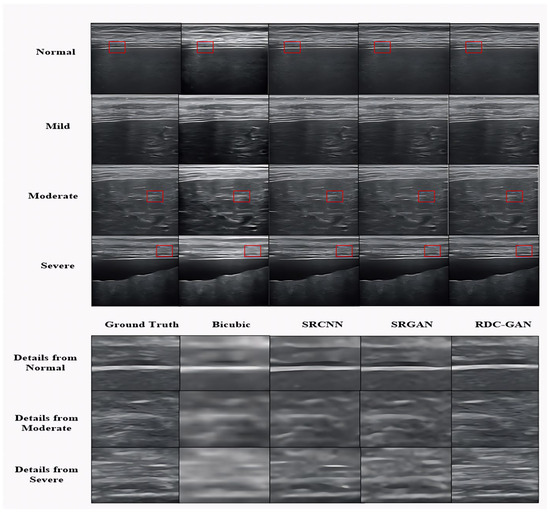

4.2. Qualitative Analysis